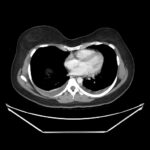

Ovarian hyperstimulation syndrome (OHSS) is a potentially life-threatening complication of assisted reproductive technology (ART). Here, we present the case report of a 30-year-old female undergoing infertility treatment who presented to the emergency department (ED) with nausea and vomiting, abdominal distention, and shortness of breath. On physical exam, she had notable ascites. Computed tomography (CT) of the abdomen and pelvis and pelvic ultrasound (US) revealed significant ascites and enlarged ovaries with multiple cysts. She was diagnosed with severe OHSS and admitted to obstetrics and gynecology (OBGYN) service for five days where she underwent intravenous (IV) hydration and paracentesis. This case report reviews the clinical presentation, categorization, management, and prevention of OHSS and provides examples of imaging findings consistent with the condition.